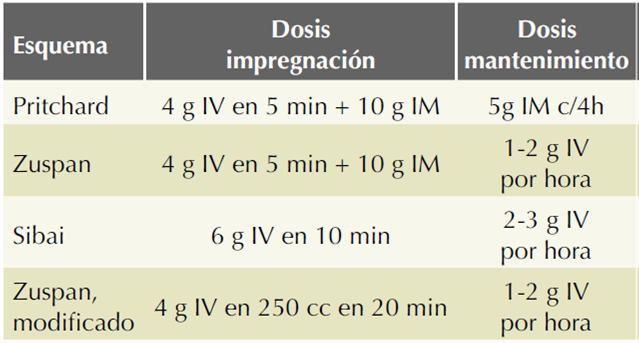

El tratamiento de la emergencia hipertensiva se inició con hidratación endovenosa, por doble vía periférica, cuantificación de la orina por sonda vesical, esquema de Zuspan modificado (Cuadro 1) de sulfato de magnesio13 (dosis de impregnación con 4 g en 30 minutos y 1 g por hora, como dosis de mantenimiento) y 10 mg de nifedipino por vía oral, como dosis única. A los 20 minutos posteriores a la toma de los medicamentos la tensión arterial se encontró en 130-85 mmHg.

Cuadro 1 Esquemas de sulfato de magnesio en preeclampsia

Fuente: Tukur J. The use of magnesium sulphate for the treatment of severe pre-eclampsia and eclampsia. Annals of African Medicine 2009;8(2):76-80. Sibai B. Diagnosis, prevention, and management of Eclampsia. American College of Obstetricians and Gynecologists 2005;105(2):402-10.